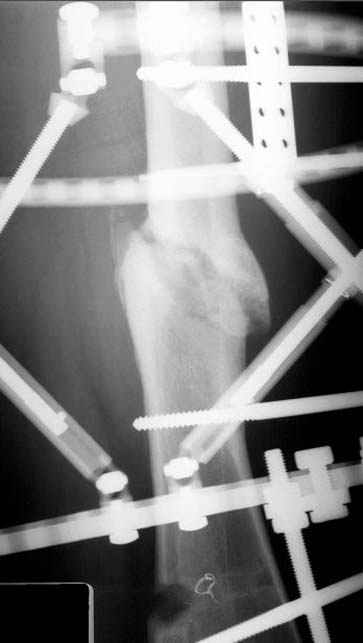

Отправитель: Djoldas Kuldjanov 23 Ноябрь 2004, 18:21

пластическая модель; и коррекция бедра аппаратом Илизарова.

Имею другие снимки тоже, получится как отчет о моей работе.